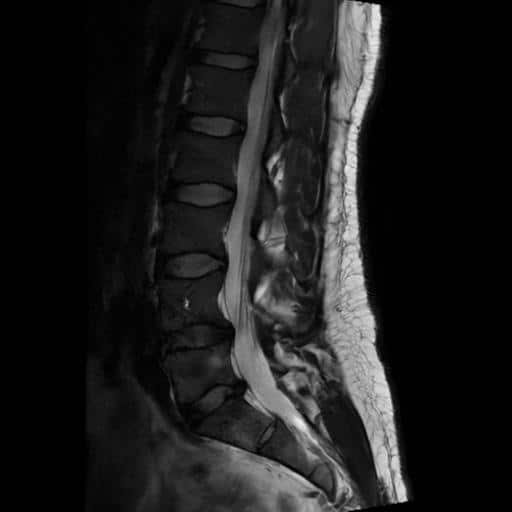

I got an MRI from a radiology clinic and confirmed that there was compression at the S1 nerve root. This at least ruled out more serious complications, but it also showed that we could really target that for recovery.

The injection was quick and easy. Just a couple of small pricks. First, the local anaesthetic, and then the injection. The radiologist looked at the imaging, and along with my symptoms, confirmed everything was consistent with an S1 nerve root inflammation. So that’s what he targeted.